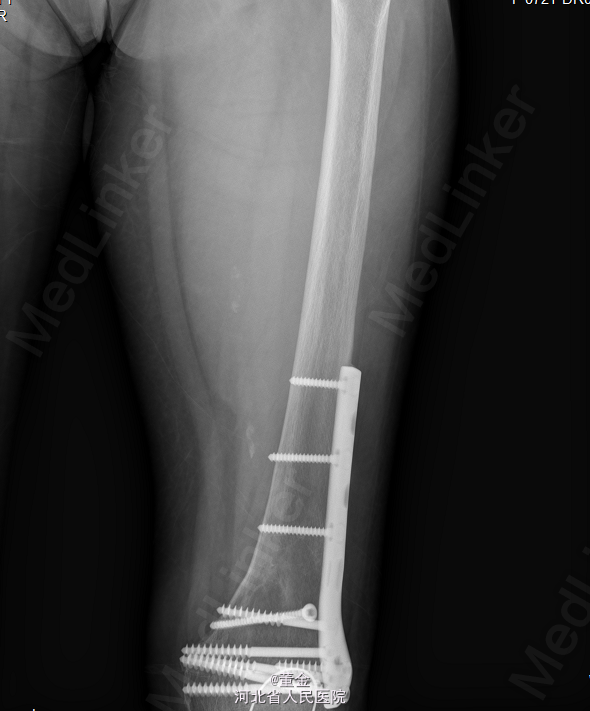

左大腿内侧可见大面积肿块,质硬,活动可,无压痛,表面皮肤无破溃。四肢末端麻木感,末梢血供正常,病理征未引出。MR1.左大腿肌间隙恶性肿瘤,平滑肌肉瘤可能性大,神经鞘瘤恶变待排。2.左股骨下段内固定术后。DR:腰椎内固定术后改变.